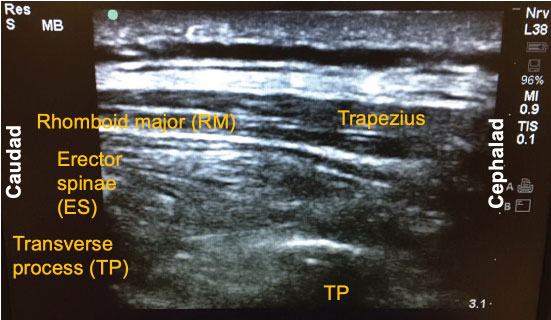

Since its introduction a few years ago, there have been numerous descriptions published on how to perform the ESP block. The following is a brief summary of the technique used to perform the block on our previously-described patient. With the patient in the sitting position, a high-frequency linear ultrasound probe was placed longitudinally on the patient's back approximately 3 cm lateral to the 5th thoracic (T5) spinous process. Three muscles above the hyperechoic transverse process were identified: trapezius, rhomboid major, and erector spinae in order of superficial to deep layers (Figure 1). A 10-cm 18-gauge Tuohy needle was inserted in-plane with the ultrasound beam at a 30° angle in a cephalad to caudal fashion. The tip of the needle was directed to the myofascial plane between the erector spinae muscle and the T5 transverse process (Figure 2). Following negative aspiration of blood, 20 mL of 0.25% ropivacaine was incrementally injected. Linear fluid spread deep to the erector spinae muscle was visualized in real-time. Finally, for continuous postoperative infusion, a 20-gauge catheter was threaded through the Tuohy needle and secured at the skin with a goal of having 5 cm of catheter left in the myofascial plane.

Figure 1: Three muscle layers for the erector spinae plane (ESP) block: Trapezius, rhomboid major (RM), and erector spinae (ES).